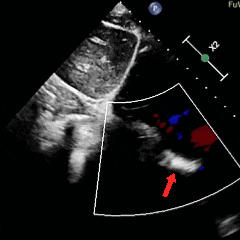

术后1周复查心脏彩超提示可降解封堵器形态位置良好,无残余分流,周围其他结构无异常。

术后1月随访,患者自述症状较前明显减轻,复查心脏彩超提示可降解封堵器形态位置良好,无残余分流,周围其他结构无异常。

术后即刻超声多切面评估显示封堵器位置正确、形态良好、夹持稳定,封堵成功;术后1周及1个月复查心脏彩超提示封堵器形态与位置稳定,无残余分流,周围结构未见异常,随访期间未再发TIA,且患者自述视物模糊、偏头痛及伴随症状均明显改善,期待后续进一步随访结果。